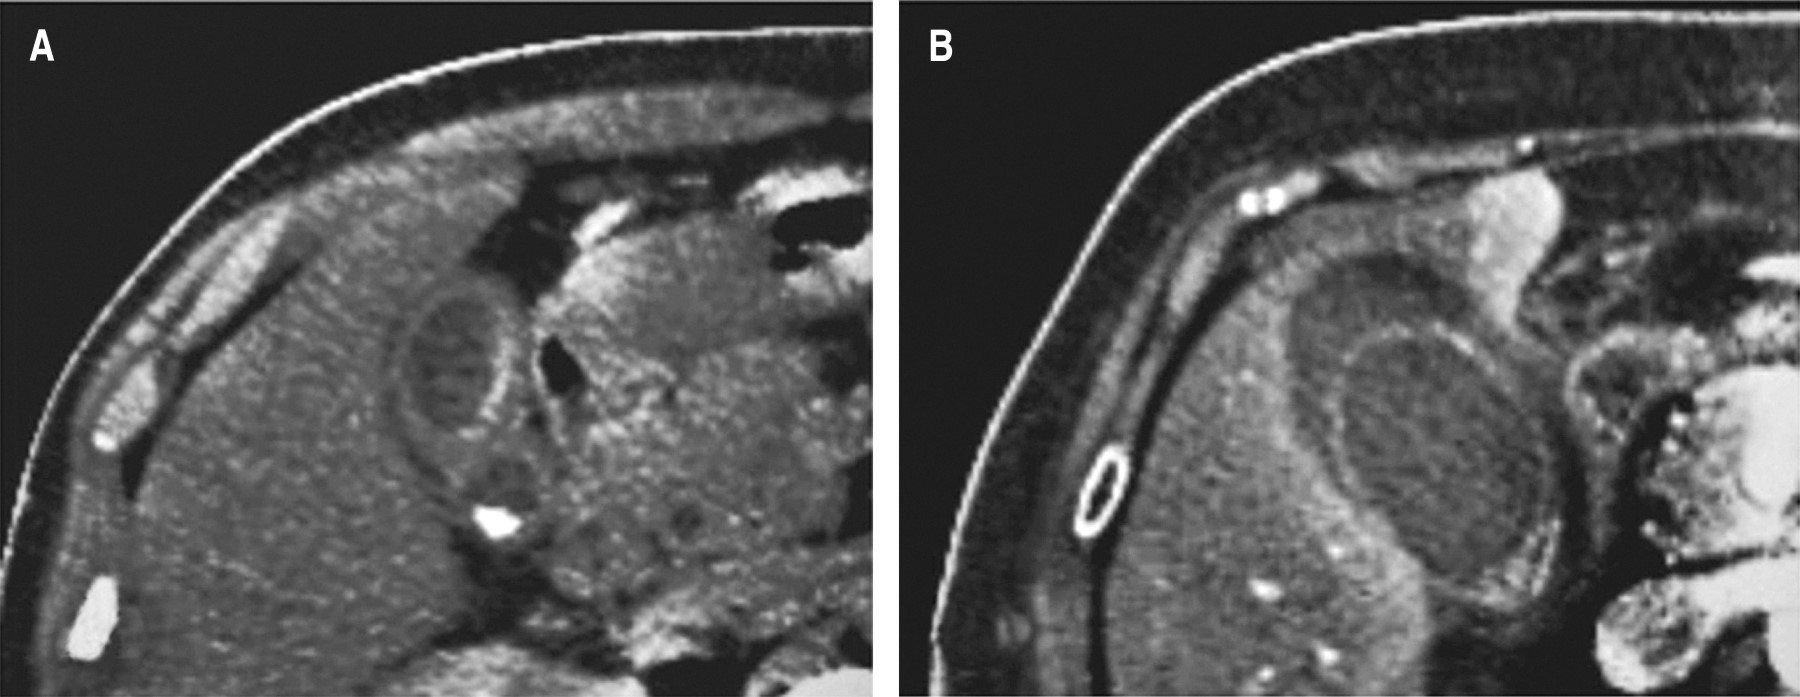

Figura 2